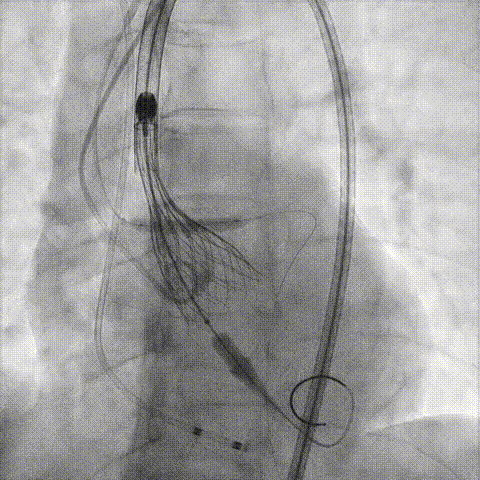

回收后调整深度,再次释放

评估左冠开口

左冠开口切线位造影

决定左冠烟囱支架保护冠脉

调整支架位置

释放冠脉支架

释放瓣膜